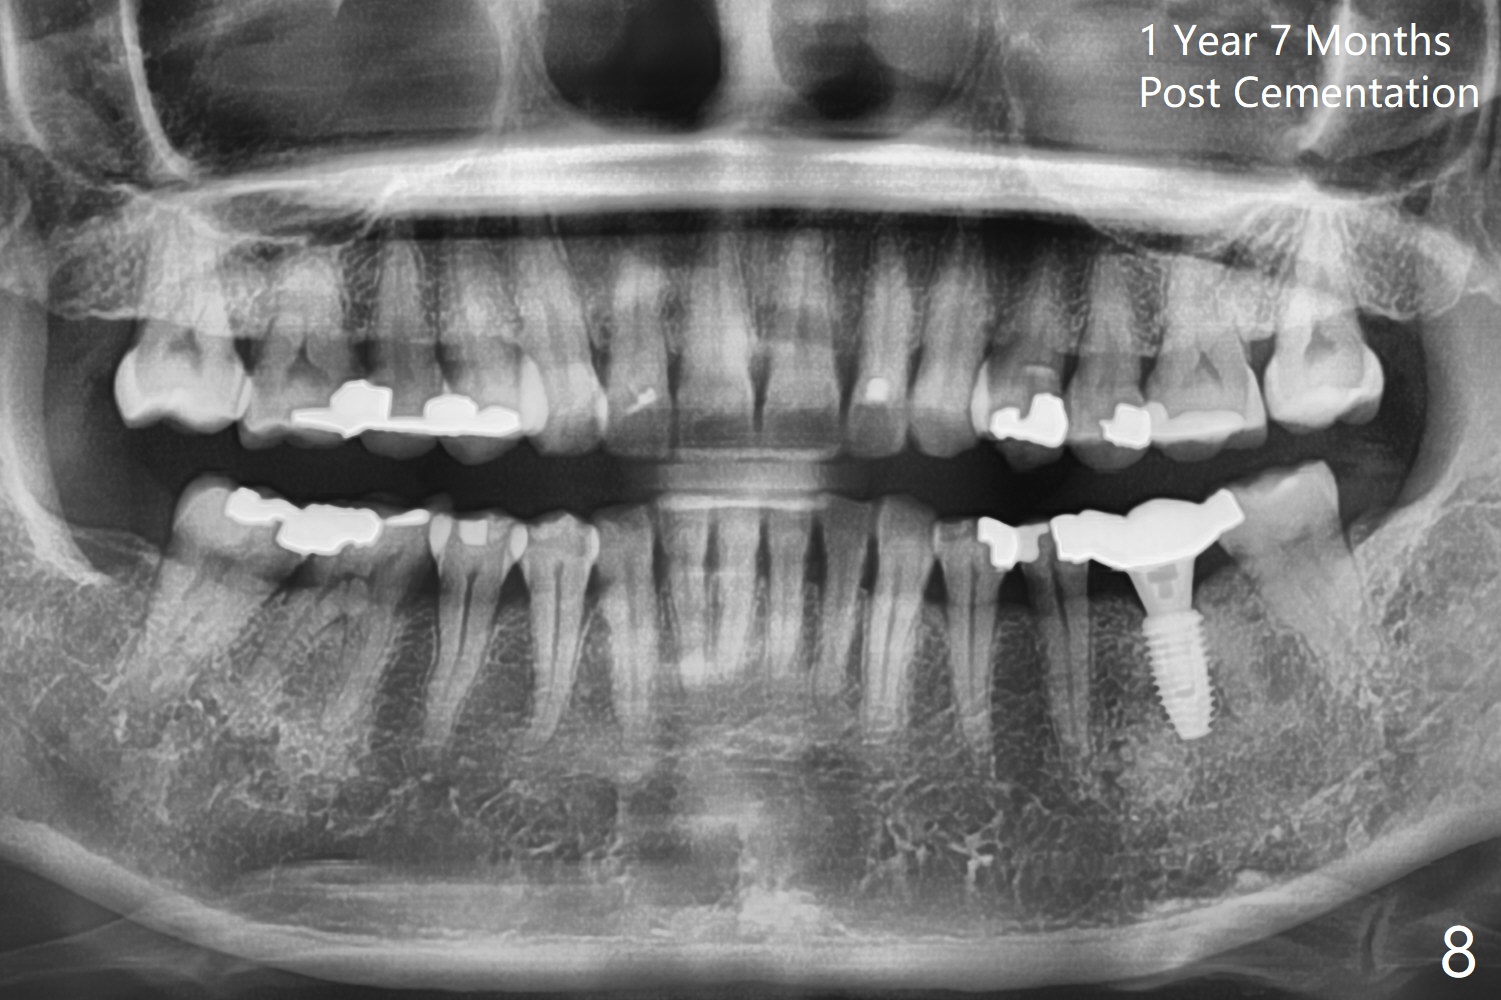

The ridge at #19 is slightly atrophic 5 months post socket preservation (Fig.1). The bone is long enough to hold a 11.5 mm long implant. There is no difficulty in inserting the corresponding drill (4.5x11.5 mm) into the metal sleeve, but the lower right posterior teeth prevent the implant handpiece from going downward completely when the handpiece accesses lingually. Because of the extra manipulation, a 5x10 mm implant achieves insertion torque of ~ 20 Ncm (Fig.2). The implant seems to be seated in the middle of the ridge (Fig.3). The bone density mesial to the implant increases 5 months postop (Fig.4), whereas that distal to the implant remains low 9 months postop (Fig.5). Bitewings taken 2.5 months post cementation (1 year postop, Fig.6,7) show subcrestal placement of the implant (advantage of guided surgery). The implant appears to be well protected; the crestal bone seems to cover the implant plateau. There will be little chance of thread exposure over years of use. The trabecular pattern around the implant is similar to that around the roots of the tooth #30 one year 7 months post cementation (2 years 4 months postop, Fig.8).